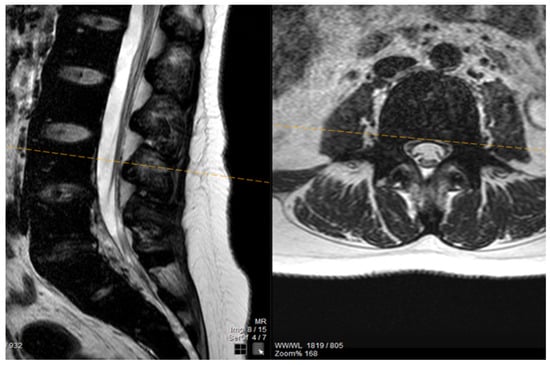

The patient noted a gradual improvement in neurological manifestations related to mobility and sensitivity. Upon discharge, she continued self-catheterization due to incomplete restoration of urination. Subsequently, the patient maintained subcutaneous iron chelation treatment with deferoxamine at a dosage of 80 mg/kg. Severe aplasia occurred two months after initiating hydroxyurea, leading to the discontinuation of both deferiprone and hydroxyurea until complete hematological recovery. Despite efforts to reintroduce hydroxyurea, the patient experienced aplasia again, prompting the decision to permanently cease this medication. Six months after the initial symptom onset, MRI findings indicated a reduction in mass and iron deposition (Figure 3 and Figure 4). The patient continued intensive iron chelation therapy with a combination of deferiprone and deferoxamine, resulting in a decreased iron load. Transfusions were maintained every 15 days with the goal of achieving hemoglobin levels above 10 g/dL. The patient achieved complete neurological recovery in the sensory and motor aspects, with only a minor improvement noted in neurogenic bladder dysfunction. Despite our patient experiencing severe myocardial iron overload, she maintained satisfactory systolic function in both the left and right ventricles. There were no observed valvular or conduction abnormalities, and the volume overload resulting from hypertransfusion did not adversely affect her overall cardiac function.

Figure 4.

The MRI findings six months after the first appearance of symptoms showed a decrease in mass and iron deposition.